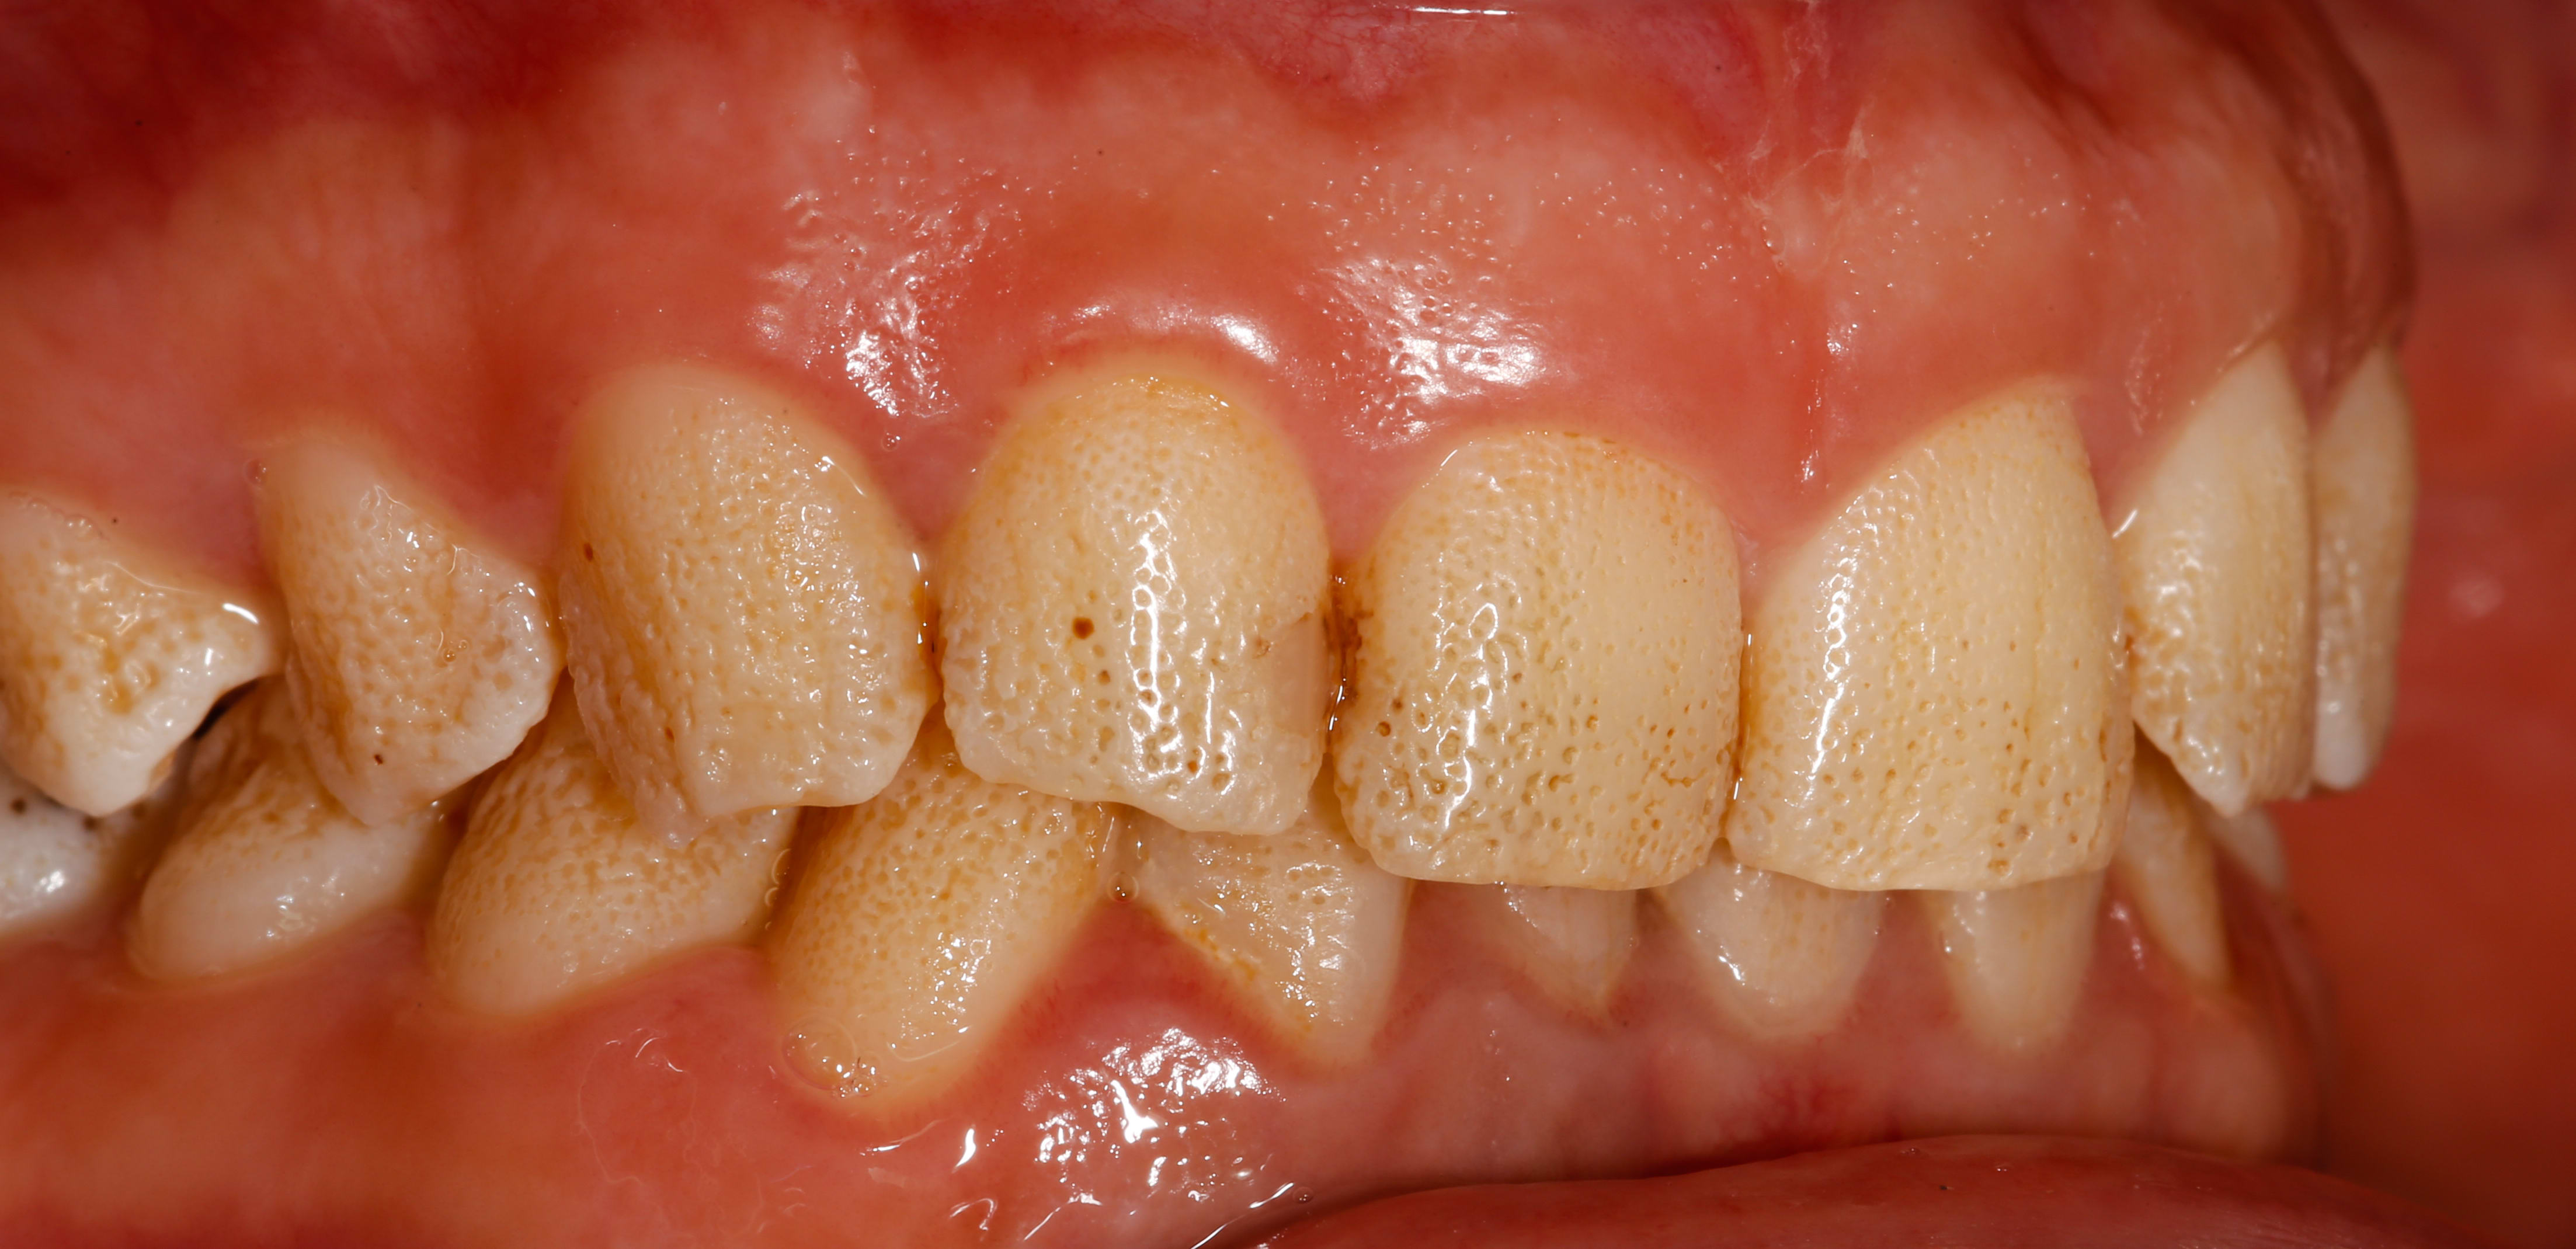

Là je cale... Je suis tombé sur ce sourire chez une patiente de 30 ans, pas de problème de santé notable, et j'ai eu beau chercher pendant l'interrogatoire ou dans les bouquins une raison pour expliquer cet aspect grêlé de l'émail, j'en ai pas trouvé une seule !

Toutes les dents définitives sont concernées, émail vestibulaire comme palatin. Ca a toujours été comme ça dans les souvenirs de la patiente.

Amélogenèse imparfaite hypoplasique ponctuée, yu as une photo comme ça dans l'article de l'ID du 7 juillet 2021

Plutôt amélogenèse imparfaite effectivement, la fluorose donne des colorations plus marquées et des pertes plus étendues dans les stades graves; pas cet aspect pointillé qui est extrèmement régulier.

C'est bien la génétique, et l'amélogénèse imparfaite ici (prévalence 1/14 000, pas de chance), dans sa variante hypoplasique ponctuée (pas la plus discrète)

Ci joint la photo de l'article de l'information dentaire dont parlait Chic22, issu de l'article des Drs Xavier BONDIL et Gabriel DOMINICI. (Les modos, si joindre la photo pose souci, je la supprime...)